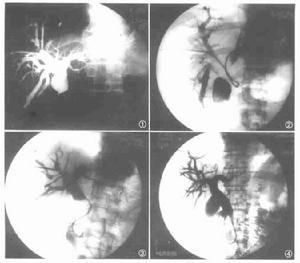

(三)經皮肝穿刺膽道造影(PTC)在肝膽管擴張病例易於成功,可清晰地顯示肝內膽管及其流向,明確有無膽管擴張和擴張的範圍。套用於黃疸病例可鑑別其原因或梗阻部位,並可觀察到膽管壁和其內部的病理改變,依其影象的特徵以鑑別阻塞的原因。

(四)經內窺鏡逆行胰膽管造影(ERCP)藉助於十二指腸鏡可經乳頭開口插管將造影劑直接注入膽管和胰管內,查明膽管擴張的範圍和梗阻部位, 並能顯示胰膽管共同通道的長度和異常情況。

(六)術中膽道造影在手術時將造影劑直接注入膽總管內,可顯示肝內、外膽管系統和胰管的全部影像,了解肝內膽管擴張的範圍、胰管膽管的返流情況, 有助於選擇術式和術後處理。